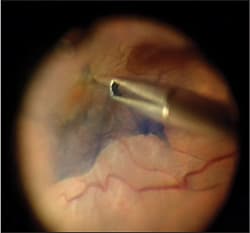

Some ERMs are subtle and difficult to visualize, yet they may be clearly seen on optical coherence tomography scanning and may be symptomatic in select patients. Intraoperatively, the ERM may be difficult to visualize and it may not be possible to identify an edge. This can lead to incomplete peeling or, in some cases, no peeling, if the ERM cannot be identified. Inability to remove the ERM or excessive retinal trauma are undesirable in a patient with a symptomatic 20/30 ERM. Staining with Membrane Blue solves this problem, allowing safe and complete ERM removal (Figure 1).

IMAGES COURTESY OF BRIAN C. JOONDEPH, MD, FACS

Figure 1. Partially peeled epiretinal membrane stained with Membrane Blue.